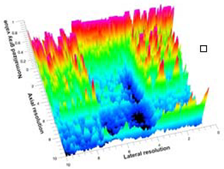

3.3. B-Mode Images

3.5. Echogenicity

4.1. Ultrasonography and Aerogel Dimensional Analyis

| Aerogel Type | US Image | Normalized Intensity Map | 3D Intensity Map | |

|---|---|---|---|---|

| 1 | Muscle |  |  |  |

| 2 | X-silica |  |  |  |

| 3 | X-silica-La2O2S:Eu |  |  |  |

| 4 | SMPU-Mix-14 |  |  |  |

| 5 | SMPU-Mix-18 |  |  |  |

| 6 | BRF-CA |  |  |  |

| 7 | ARF-CA |  |  |  |

| 8 | X-Ca-Alg-2 |  |  |  |

| 9 | X-Ca-Alg-1 |  |  |  |

| Aerogel Type | Imaging Frequency (MHz) | Optimal Frequency (MHz) | Echogenicity | Image Characteristics | Impedance Mismatch (%) | |

|---|---|---|---|---|---|---|

| Subcutaneous | Submuscular | |||||

| X-silica | 6.5–13.4 | 13.4 MHz | Hypoechoic | Least Hyperechoic | Distinct linear boundary | 92.03 |

| X-silica-La2O2S:Eu | 6.5–13.4 | 13.4 MHz | Hypoechoic | Least Hyperechoic | Distinct linear boundary | 90.28 |

| SMPU-Mix-14 | 6.5–13.4 | 11 MHz | Hyperechoic | Moderately Hyperechoic | Irregular boundary | 98.33 |

| SMPU-Mix-18 | 6.5–13.4 | 11 MHz | Hyperechoic | Moderately Hyperechoic | Irregular boundary | 98.23 |

| BRF-CA | 6.5–13.4 | 13.4 MHz | Hyperechoic | Hyperechoic | Waterfall appearance | 97.16 |

| ARF-CA | 6.5–13.4 | 13.4 MHz | Hyperechoic | Hyperechoic | Waterfall appearance | 97.12 |

| X-Ca-Alg-2 | 6.5–13.4 | 11 MHz | Isoechoic | Strongly Hyperechoic | Irregular boundary | 98.03 |

| X-Ca-Alg-1 | 6.5–13.4 | 11 MHz | Isoechoic | Strongly Hyperechoic | Irregular boundary | 97.97 |